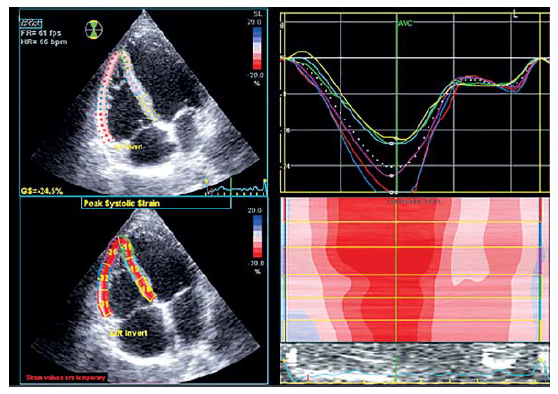

Глобальная продольная деформация (GLS) ПЖ является воспроизводимой и доступной методикой оценки глобальной систолической функции и рассчитывается как процент систолического укорочения свободной стенки ПЖ от основания к верхушке. Продольная деформация зависит от формы, размера ПЖ, качества и доступности изображения ПЖ. Значение GLS ПЖ больше –20% считается патологическим (рис. 13).

Рис. 13. Измерение GLS ПЖ в режиме Speckle tracking

В соответствии с рекомендациями EACVI (2017), патологическим принято значение общего продольного систолического стрейна для свободной стенки ПЖ (GLS) больше –23%. Определение общего продольного систолического стрейна свободной стенки ПЖ возможно арифметически (среднее из показаний по трем сегментам ПЖ в методике 6 или 3 сегментов) или по систолическому пику кривой среднего стрейна ПЖ (в методике 3 сегментов) [7]. Клиническое применение стрейна ПЖ заключается в определении субклинических изменений (до изменения параметров стандартной ЭхоКГ и ФВ ПЖ в 3D-режиме), динамической оценки терапевтического эффекта и прогноза. При исследовании прогностического значения GLS правого желудочка А. Sachdev et al. [9] обнаружили, что прогрессирование симптомов легочной гипертензии в 2,5 раза чаще определялось при снижении GLS ПЖ<20%, и более, чем в 20 раз – при снижении GLS ПЖ<12,5%. Аналогично снижалась выживаемость данных пациентов. Смертность от всех причин была также выше среди пациентов с GLS ПЖ<15%.